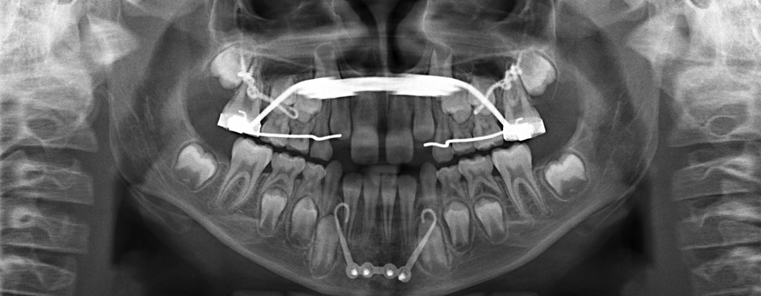

Mentoplates

Bei den Mentoplates handelt es sich um spezielle kieferorthopädische Knochenplatten. Diese können auf Wunsch der behandelnden Kieferorthopädin oder des behandelnden Kieferorthopäden in unserer Klinik für Mund-, Kiefer- und Gesichtschirurgie am UKS in einem kleinen operativen Eingriff von der Mundhöhle aus am Knochen des Ober- und Unterkiefers fixiert werden.

Die Mentoplates dienen dazu, das Kieferwachstum zu beeinflussen. Sie werden insbesondere im Rahmen der Frühbehandlung bestimmter Kieferfehlstellungen eingesetzt, bei sogenannten Klasse-II- und Klasse-III-Anomalien. Somit können unkomfortable kieferorthopädische Geräte wie Gesichtsmasken oder Kopf-Kinn-Kappen, welche außerhalb der Mundhöhle am Kopf getragen werden müssen, zum Teil vermieden werden.